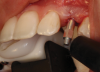

(44.) The provisional restoration was placed back on the implant and tightened to 15 Ncm while applying counter torque. Note that the papillae are partially supported without pressure and that the gingival embrasures are slightly open to allow incisal migration of the papillae during the integration and maturation phase.

Figure 44